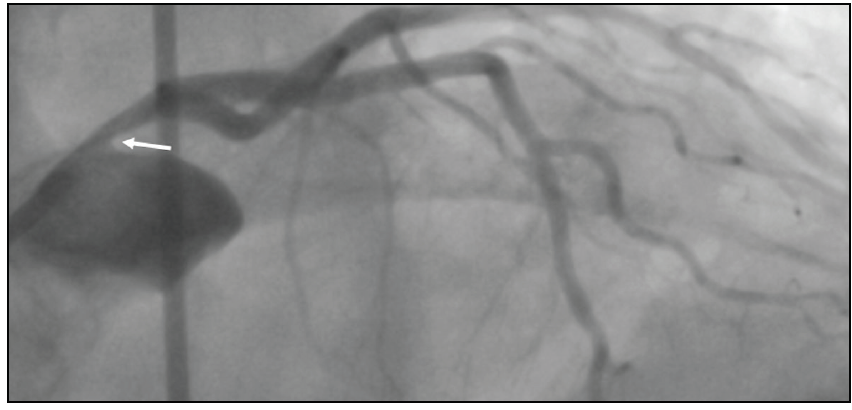

Chest radiation therapy for thoracic malignancies, such as lung and breast cancer as well as Hodgkin lymphoma, is also known to produce accelerated atherosclerosis with increased rates of fatal and nonfatal myocardial infarction (MI) compared to the nonexposed population.22 The classic angiographic features are severe ostial or proximal epicardial lesions, which include left main (LM) trunk, proximal left anterior descending artery, or proximal right coronary artery stenosis due to their anterior or central mediastinal location that makes them more susceptible to higher doses of radiation compared to other areas (Figure 1 and Figure 2).23

Figure 1. Refractory radiation-induced coronary artery disease in a 48-year-old woman with cardiovascular risk factors (hypertension, hyperlipidemia, diabetes, obesity) diagnosed with breast cancer with chest wall involvement (A) treated with radical mastectomy, chemotherapy, and radiation therapy (total of 54 Gy in 27 fractions over 5 weeks). She had accelerated atherosclerotic process and new coronary calcification on a follow-up CT scan (B). Three years later, the patient presented with acute MI (type II) and underwent PCI with three sequential DESs implanted in the distal left anterior descending artery. One year later, she returned to the hospital with NSTEMI, with coronary angiography showing disease progression and significant edge restenosis (C). Additional stents were placed, covering the gaps in an overlapping fashion, with final angiography showing good results and thrombolysis in myocardial infarction 3 flow (D). IVUS confirmed good expansion and apposition of the newly deployed stents (E). Three years later, the asymptomatic patient had a stress test that yielded abnormal results, and subsequent angiography revealed an occluded distal left anterior descending artery (F).